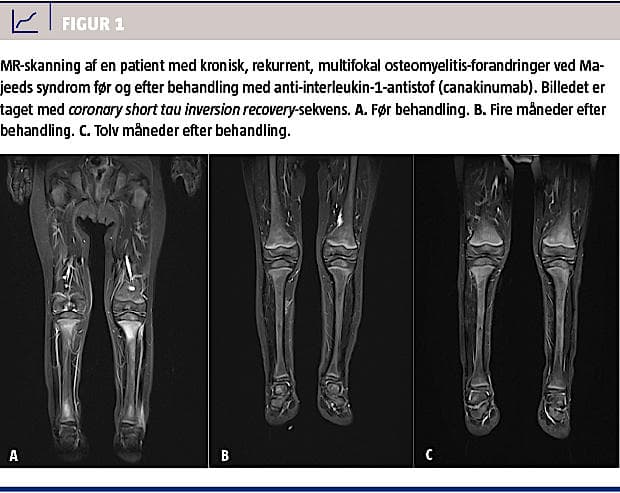

Konventionel røntgenundersøgelse kan vise osteolytiske eller osteosklerotiske læsioner, men kan i den tidlige fase vise normale forhold [9]. MR-skanning er særdeles velegnet til at afsløre de osteomyelitiske læsioner med, endda allerede på et tidligt trin, hvor der ses knogleødem, før de osteolytiske eller skleroserende forandringer opstår [9, 10]. Desuden kan man ved MR-skanning påvise associerede detaljer som periosteitis, bløddelsinflammation og ledvæskeansamling, som er fund, der ofte underestimeres ved almindelig røntgenundersøgelse. Da CNO er en systemisk sygdom, som afficerer multiple knogler, har knoglescintigrafi (99mTc-mærket methylen-difosfonat-knoglescintigrafi) været anvendt, og man har ofte fundet klinisk symptomfri læsioner. Dog kan opladning i vækstzonen hos et endnu ikke udvokset barn være svær at skelne fra metafysære forandringer set ved CRMO, hvorfor MR-skanning tit foretrækkes [11]. Helkrops-MR-skanning anvendes nu i stigende grad, både initialt i forløbet for at sikre afsløring af

ikkesymptomgivende læsioner [2, 12, 13] og som led i opfølgning af et behandlingsforløb (Figur 1). Ved knoglebiopsi finder man uspecifikke, histopatologiske forandringer med dominans af polymorfkernede leukocytter i det tidlige stadie og senere fortrinsvis plasmacelle- og lymfocytinfiltration samt evt. knogleresorption og reaktiv skleroserende knoglenydannelse [6]. Som led i diagnostikken er radiologi og biopsi vigtige redskaber til udelukkelse af differentialdiagnoser, som bl.a. malign sygdom og infektiøs osteitis.